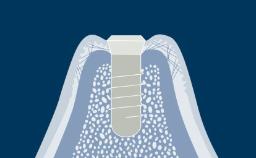

There are many conventional fixed treatment options that can be considered for the replacement of missing teeth. They include Fixed Dental Prostheses or FDPs, fixed cantilever FDPs and resin-bonded FDPs.

This module will discuss the advantages and disadvantages of conventional fixed treatment options for replacing missing teeth and compare their published treatment outcomes and indications with those of implant-supported prostheses.